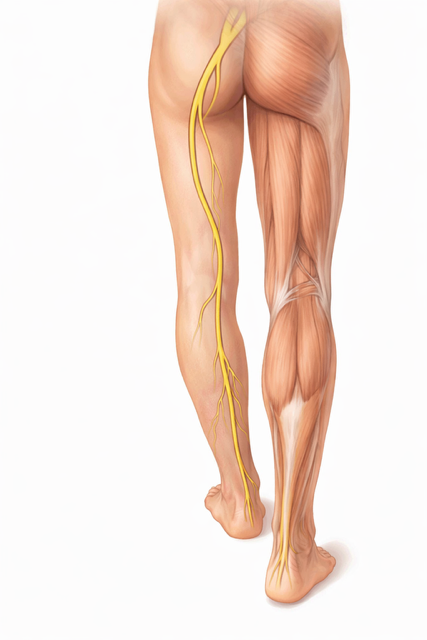

¿Entonces tiene sentido que me duela la espalda y el talón ?

Si , claro. Tiene todo el sentido ya que hay una conexión directa entre ambos, tanto a nivel biomecánico , como de conexión nerviosa.

¿Qué patologías lumbares pueden tener su origen en los pies?

Las más relevantes y frecuentes:

– Trocanteritis

– Ciáticas recurrentes

–Protusiones discales.

– Hernias discales

– Dolor sacroilíaco

– Lumbalgias crónicas

No significa que el pie sea la única causa, pero sí que es muchas veces , el desencadenante o el factor perpetuador.